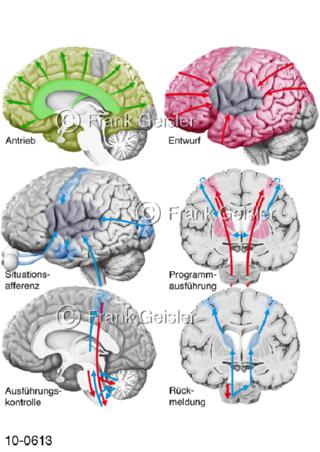

Bildergalerie Nervensystem

Bilder zum Nervensystem,dem Gehirn, Teil des zentralen Nervensystem, Zentralnervensystem ZNSmit Rückenmark, Abbildungen zum Nervengeflecht (Nervenplexus), die Verflechtungen von Nervenfasern, aus der Wirbelsäule hervortretende Nervenäst sowie Nervenzellen der Nerven